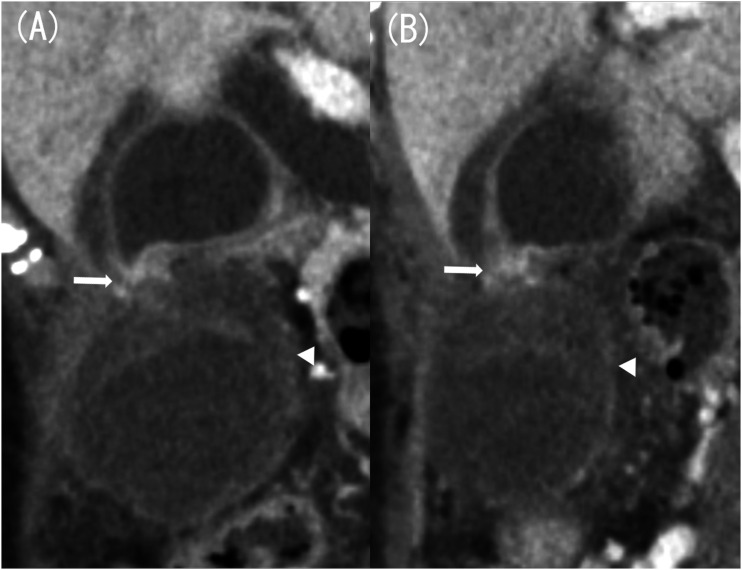

Cholecystitis is a common disease, but the occurrence of gallbladder strangulation is extremely rare. Here, we report a case of an 88-year-old woman with strangulated cholecystitis caused by an intraperitoneal band. Computed tomography (CT) scan revealed a constriction of the gallbladder body and marked wall thickening at the fundus. Additionally, the finding suggested torsion at the constricted area, which we diagnosed as gallbladder torsion. Cholecystectomy was performed immediately, and the diagnosis was strangulated cholecystitis caused by a band. The imaging findings of strangulated cholecystitis are similar to gallbladder torsion, making it difficult to diagnose preoperatively. We will discuss the imaging findings of strangulated cholecystitis and gallbladder torsion.